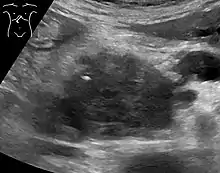

Abdominal ultrasonography of pancreatic cancer (presumably adenocarcinoma), with a dilated pancreatic duct to the right.

Medical imaging techniques, such as computed tomography (CT scan) and endoscopic ultrasound (EUS) are used both to confirm the diagnosis and to help decide whether the tumor can be surgically removed (its "resectability").[12] On contrast CT scan, pancreatic cancer typically shows a gradually increasing radiocontrast uptake, rather than a fast washout as seen in a normal pancreas or a delayed washout as seen in chronic pancreatitis.[50] Magnetic resonance imaging and positron emission tomography may also be used,[11] and magnetic resonance cholangiopancreatography may be useful in some cases.[30] Abdominal ultrasound is less sensitive and will miss small tumors, but can identify cancers that have spread to the liver and build-up of fluid in the peritoneal cavity (ascites).[12] It may be used for a quick and cheap first examination before other techniques.[51]